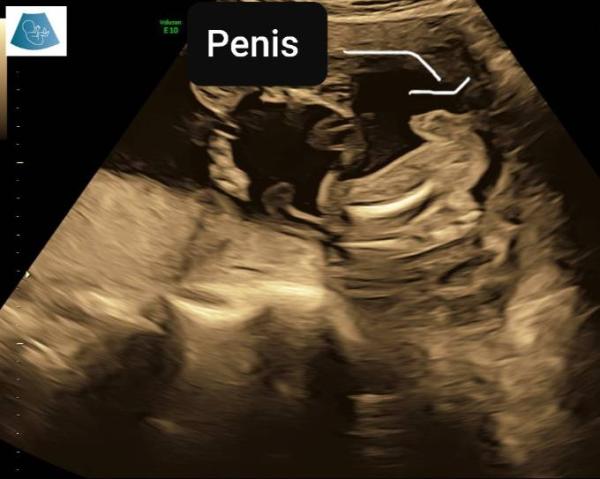

Sieht aus wie bei meinem also Team blau

denke junge

Sage auch 99%junge

Wahnsinn das sieht man ja eindeutig